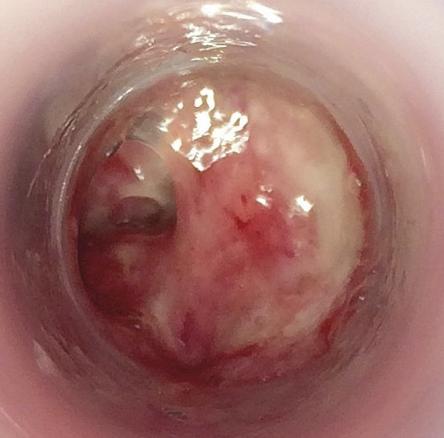

Un homme de 30 ans consulte pour une douleur ano-rectale intense évoluant depuis 24 heures avec des faux besoins glairo-sanglants. Il prend une prophylaxie pré-exposition contre le VIH. La marge anale est normale. L’anuscopie montre une rectite érythémateuse avec des sécrétions purulentes (fig. 1 ).

Le diagnostic est évoqué sur l’anamnèse et la clinique. Il est confirmé par l’analyse polymerase chain-reaction (PCR) d’un écouvillonnage rectal détectant simultanément Neisseria gonorrhoeae (fig. 2 ) et Chlamydia trachomatis. Ce prélèvement permet également la réalisation d’un antibiogramme.